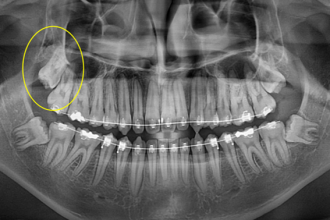

사랑니발치

굿프렌즈 치과 임상 케이스